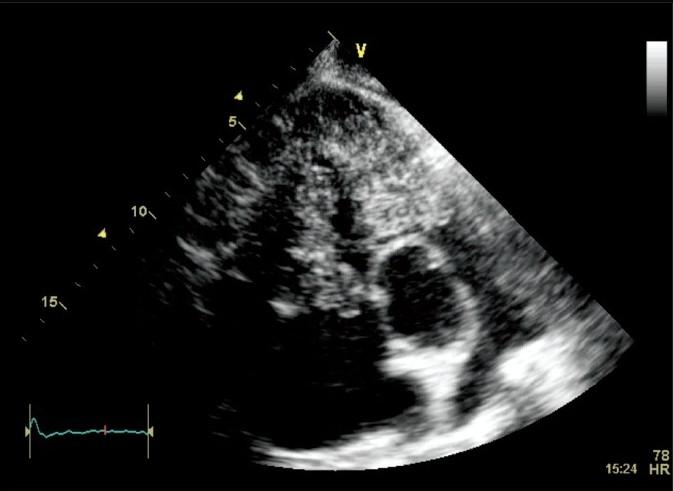

Primary cardiac sarcomas are rare tumors with unfavorable prognosis. We report a 69-year-old male with a right ventricular mass diagnosed as primary malignant cardiac sarcoma with unexpected long survival of 16.5 months.

原发性心脏肉瘤是一种预后不良的罕见肿瘤。我们报告一例69岁男性,其右心室肿块被诊断为原发性恶性心脏肉瘤,生存期意外长达16.5个月。